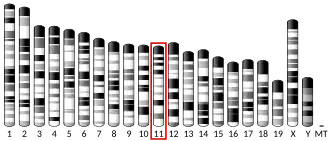

Gene

This gene encodes alpha-1B-adrenergic receptor, which induces neoplastic transformation when transfected into NIH 3T3 fibroblasts and other cell lines. Thus, this normal cellular gene is identified as a protooncogene. This gene comprises 2 exons and a single large intron of at least 20 kb that interrupts the coding region.[5]